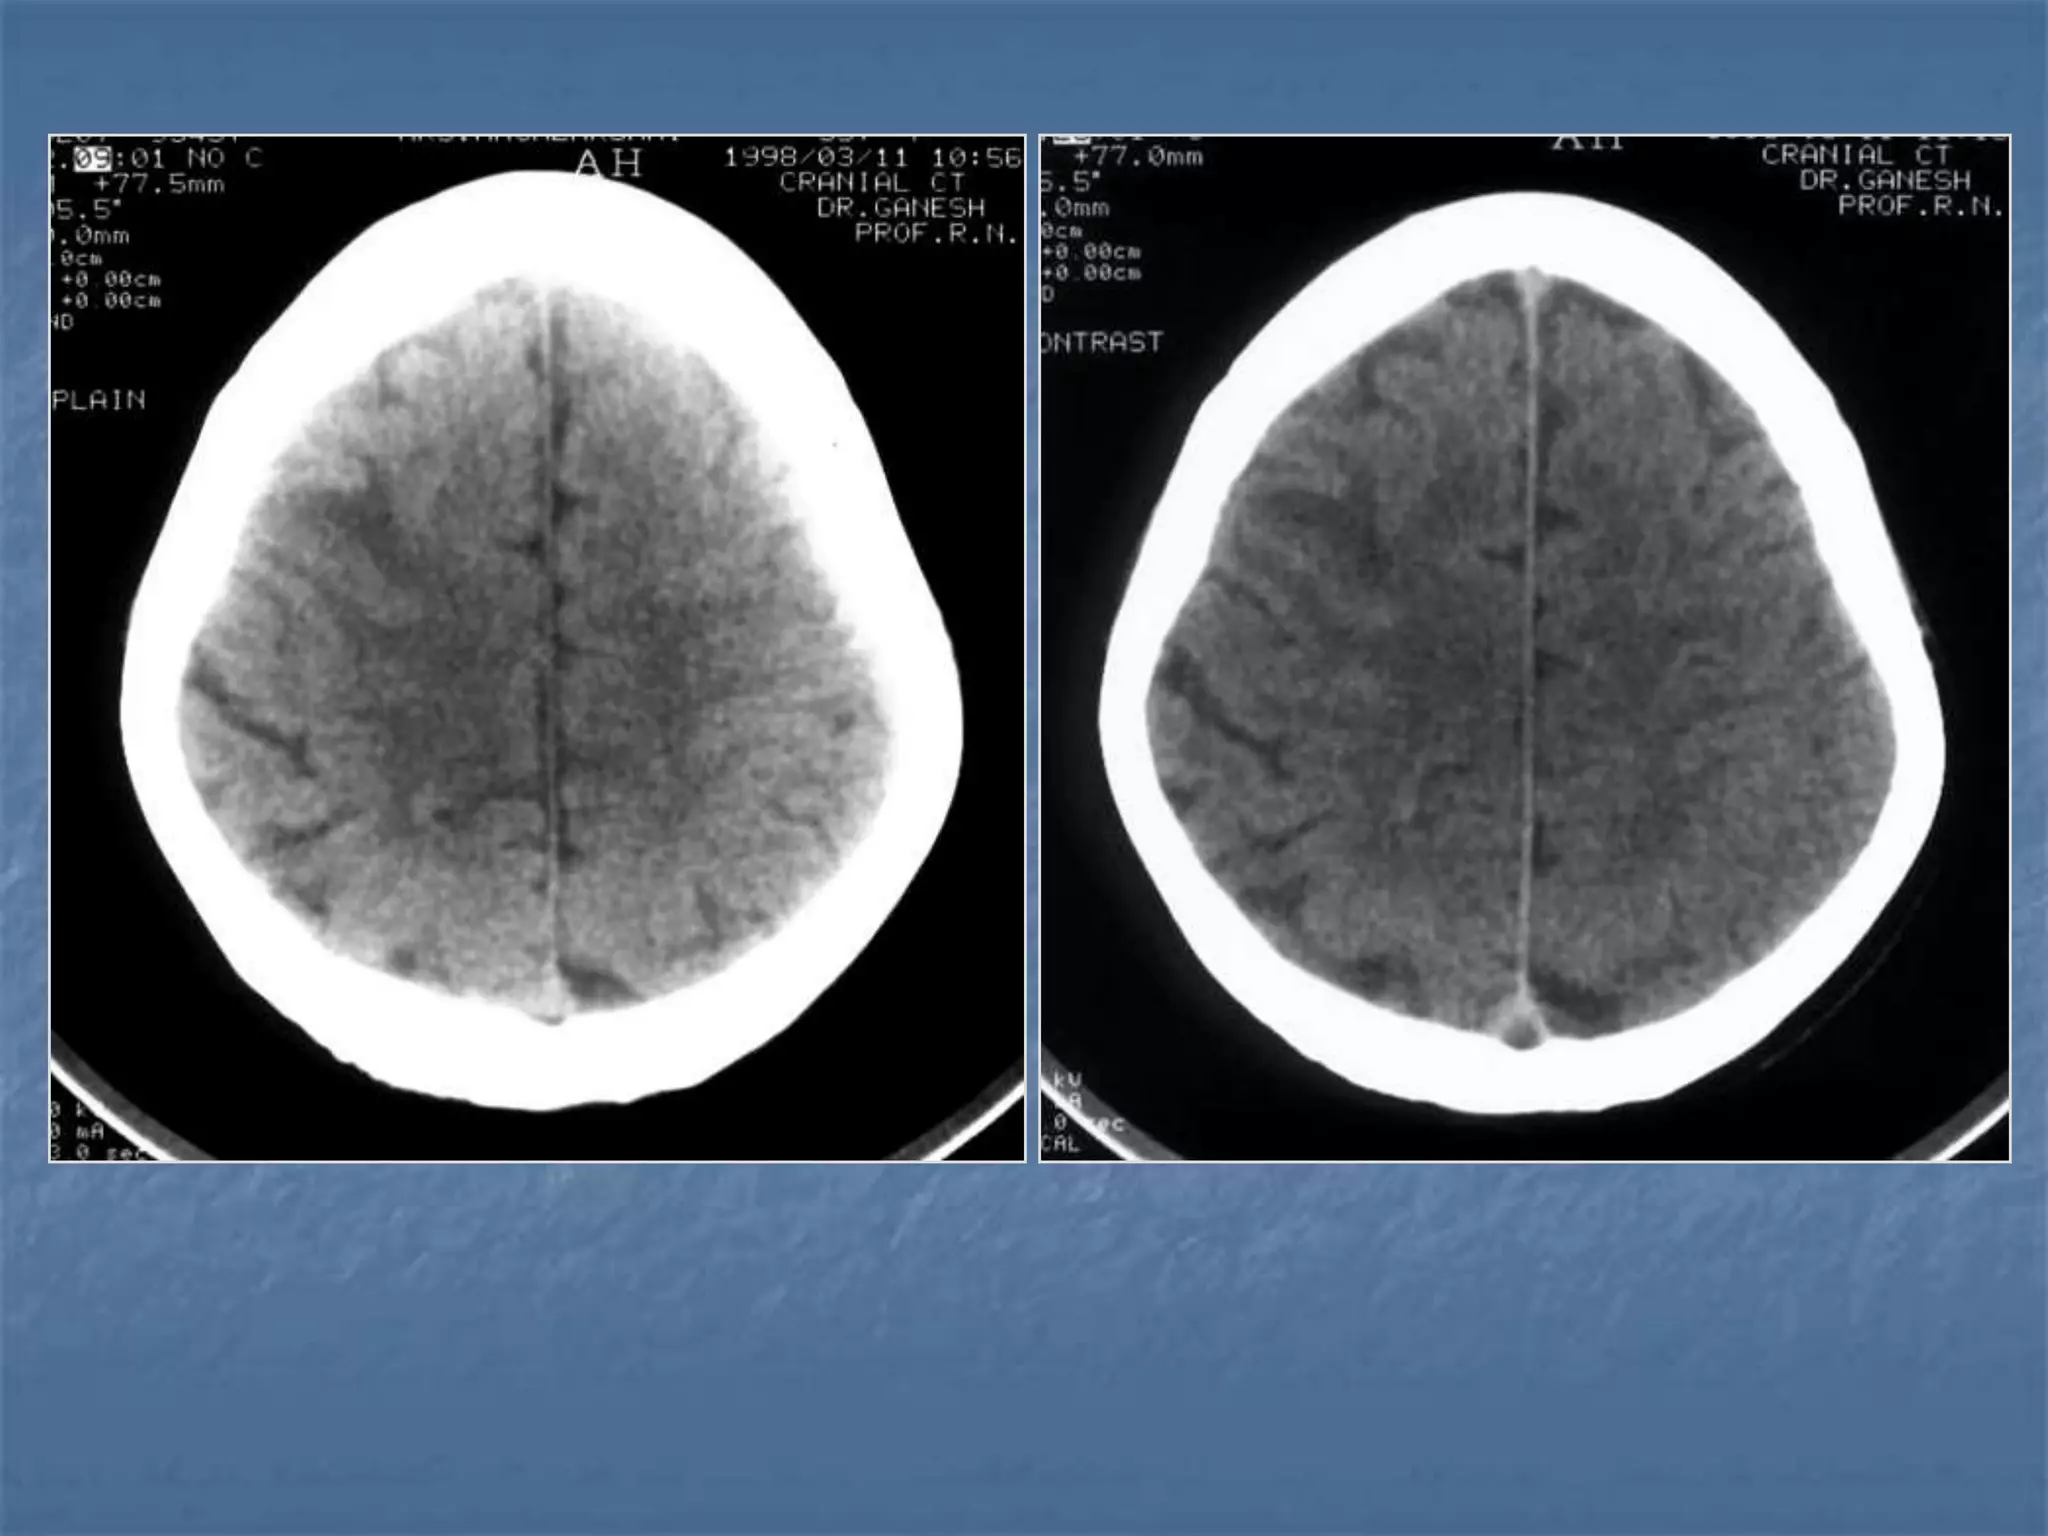

Cerebellar AtrophyCerebral Atrophy